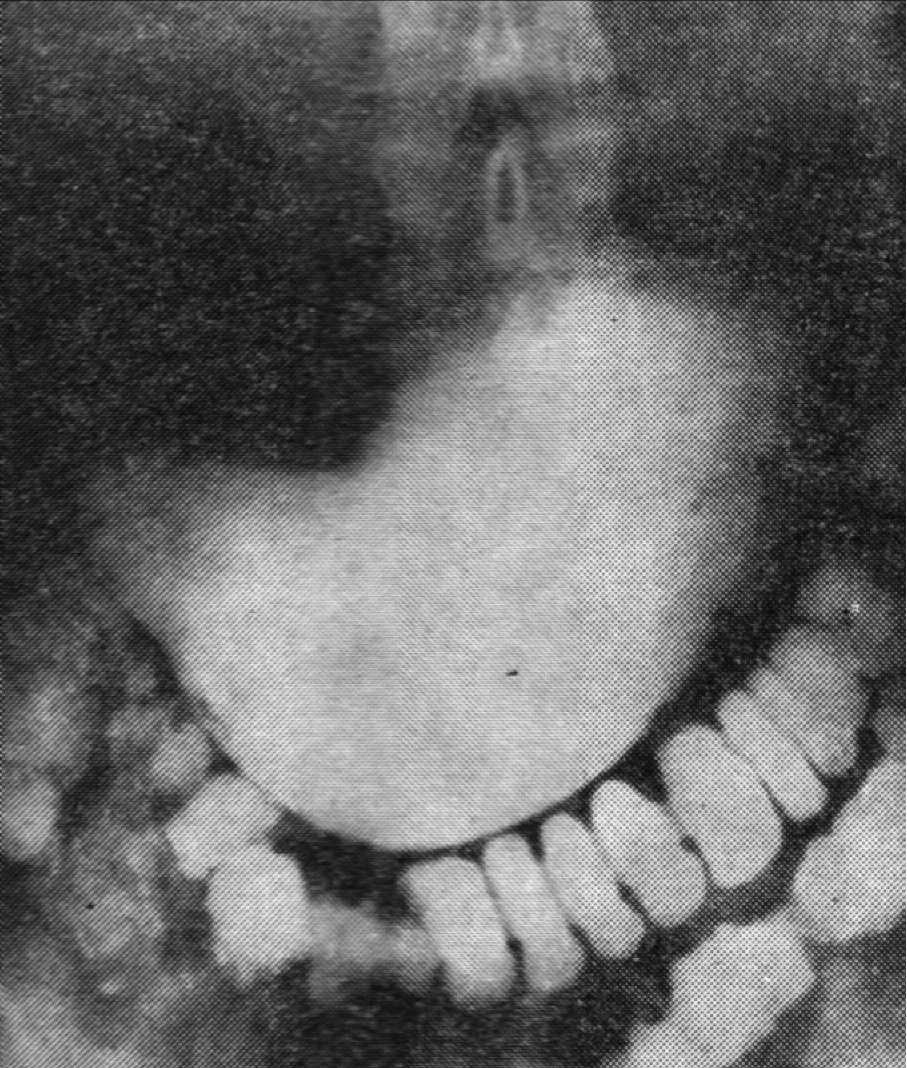

Выполнена рентгеноскопия желудка с бариевой взвесью (см. рисунок).

Рентгенограмма желудка с пассажем бариевой взвести по тонкой кишке.

Отмечается быстрая эвакуация контраста из желудка и ускоренный пассаж его по тонкой кишке. Через 30 минут небольшое количество контраста в культе желудка, большая часть контраста заполнила всю тонкую кишку до илеоцекального отдела.